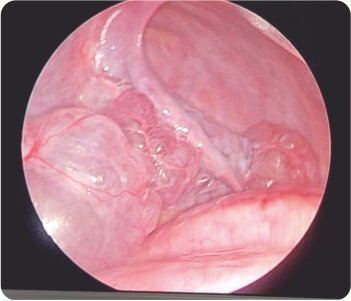

In view of the risk of recurrent pneumothorax, the patient was taken up for VATS (Video Assisted Thoracoscopic Surgery) with right sided bullectomy was done. During the hospital stay, the patient was closely monitored and the patient’s condition gradually improved and was discharged after being stabilized.

Video-assisted thoracoscopic surgery during procedure